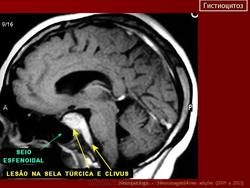

Гистиоцитоз.